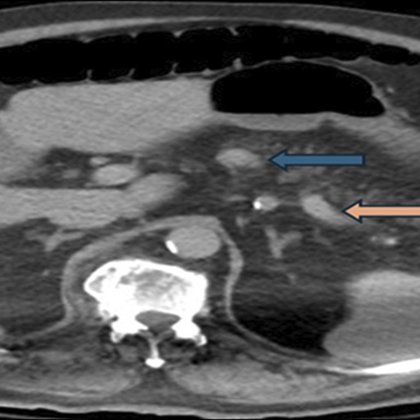

ncreatic body mass confirmed as a World Health Organization grade 1 insulinoma on histopathology. Given the high surgical risk, we performed a EUS-RFA with 13 sequential ablations. Blood glucose...